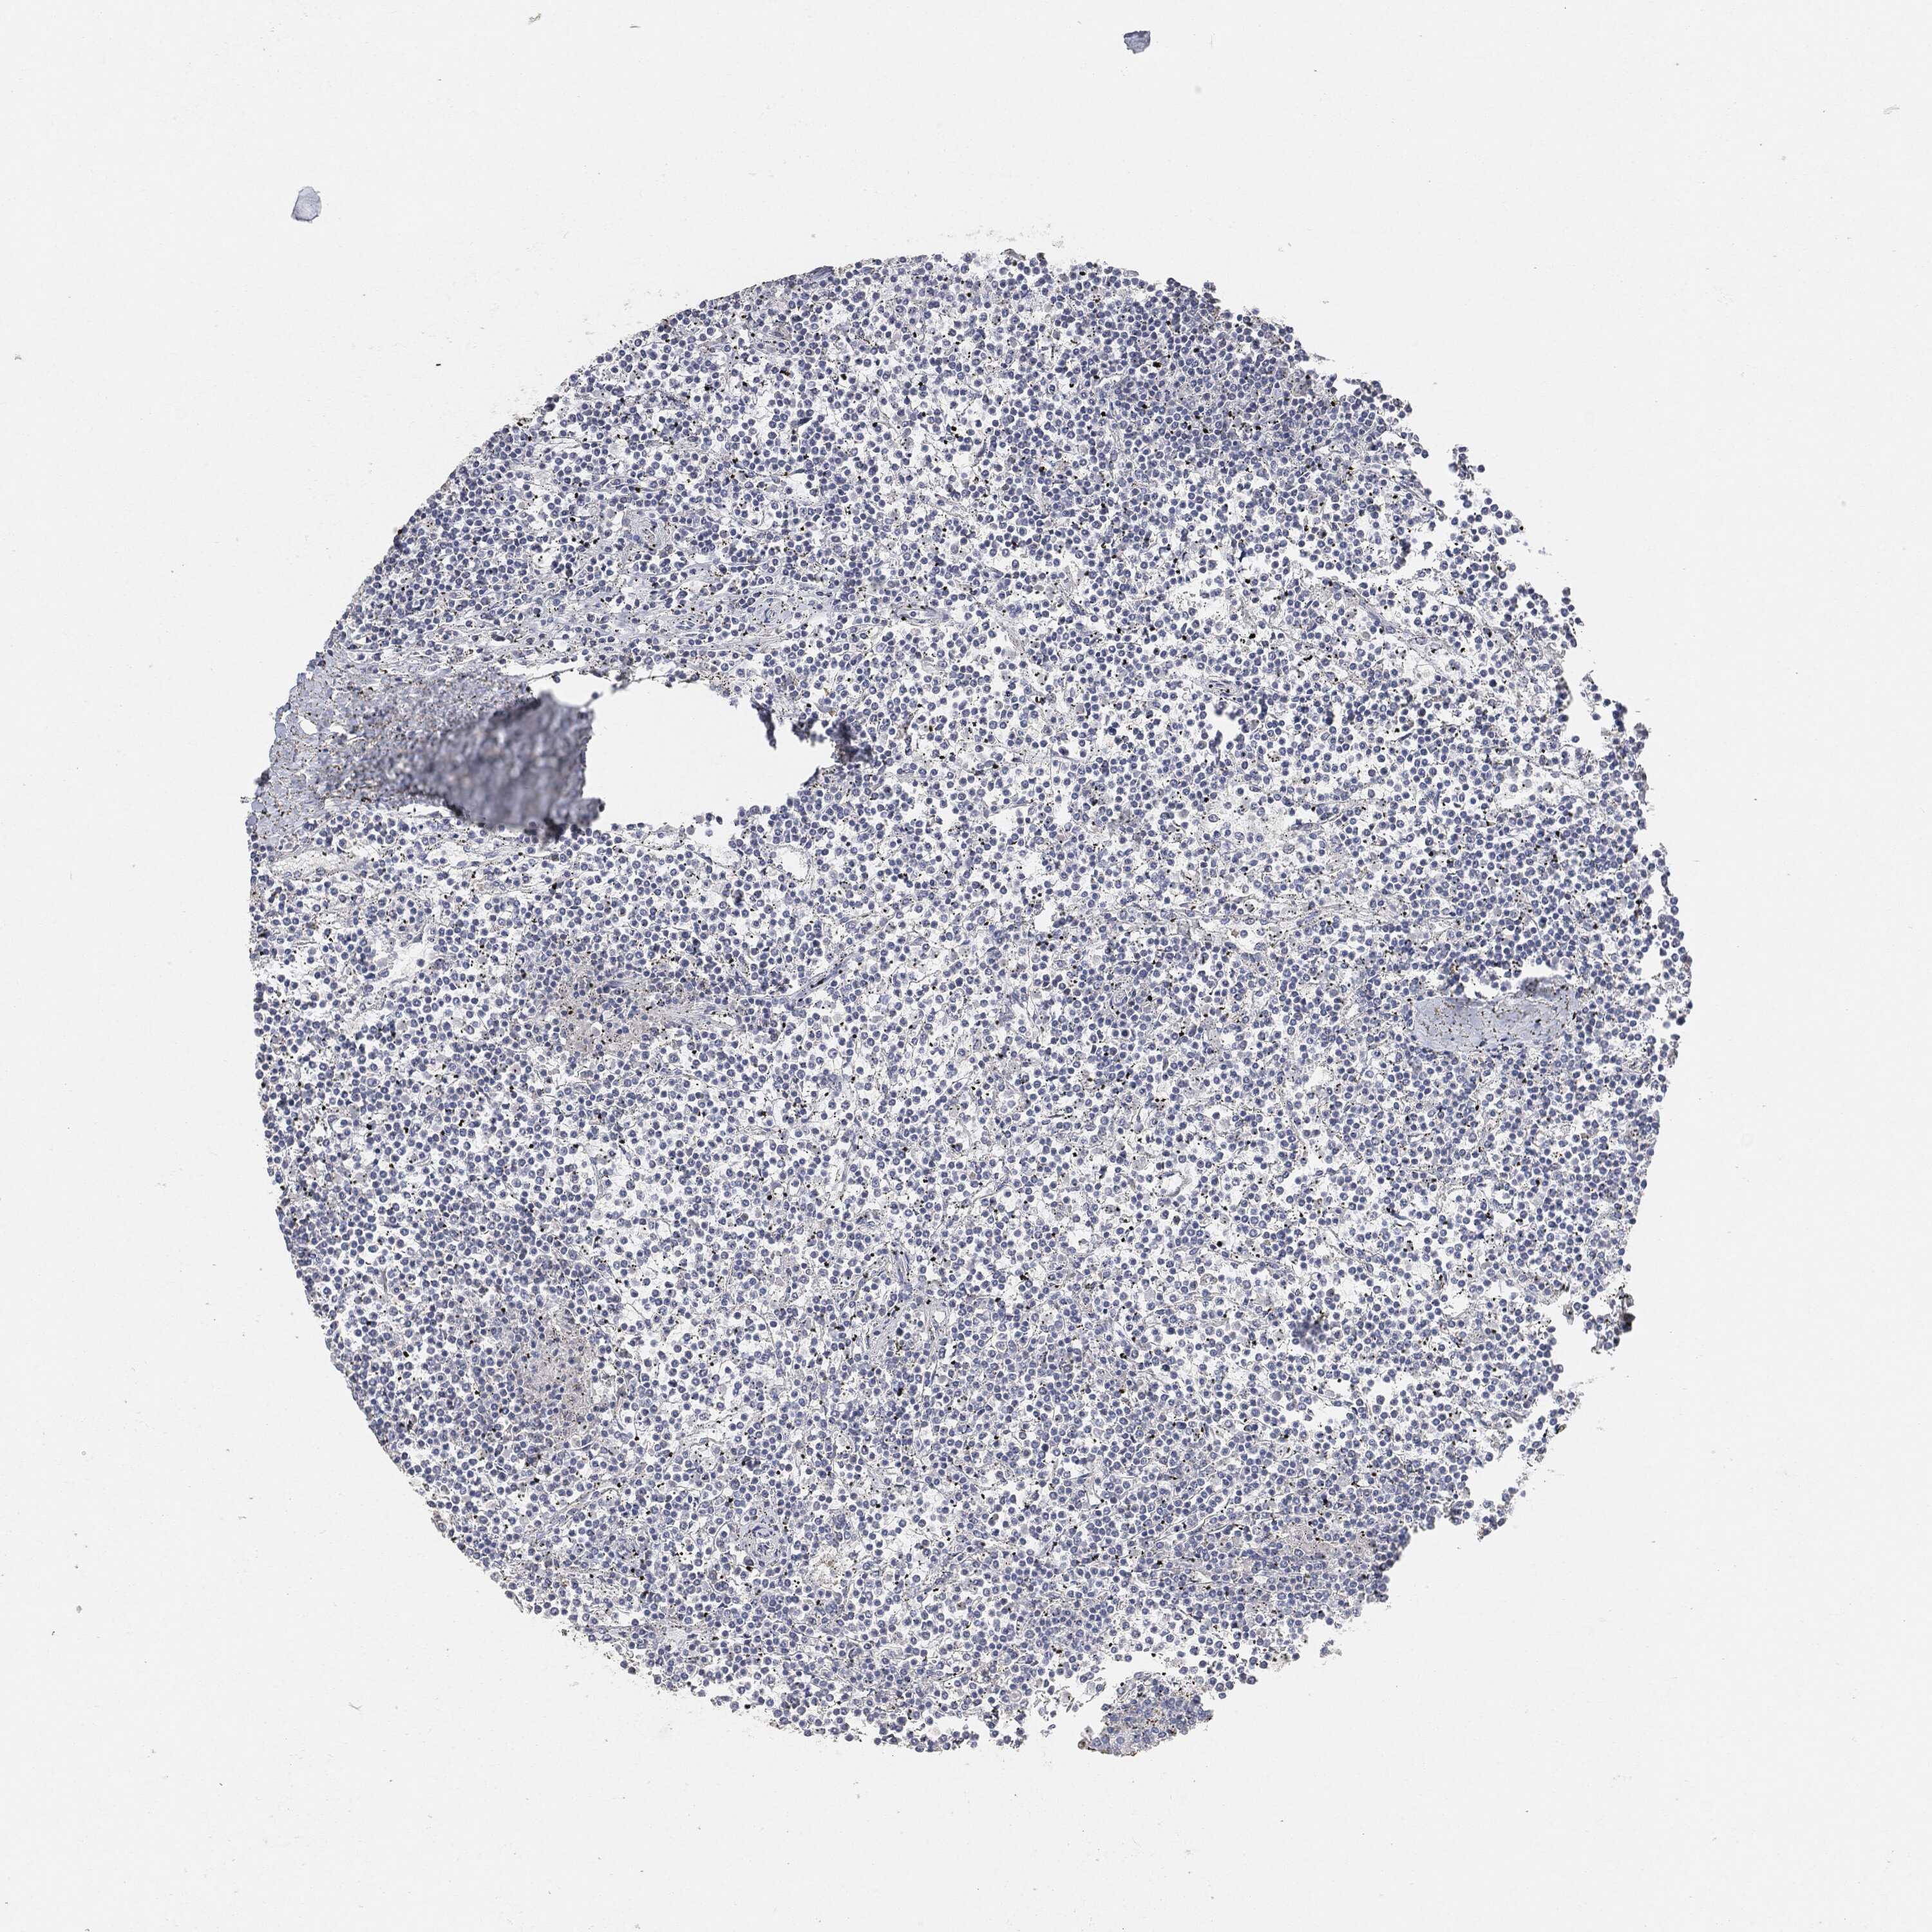

CANCER LYMPHOMA Show tissue menu

LYMPHOMA - Protein expressioni

A mouse-over function shows sample information and annotation data. Click on an image to view it in a full screen mode. Samples can be filtered based on level of antibody staining by selecting one or several of the following categories: high, medium, low and not detected. The assay and annotation is described here.

Each image is clickable and will lead to virtual microscopy that enables deeper exploration of all samples and also displays staining intensity scores, fraction scores and subcellular localization as well as patient and tissue information for each sample.

Malignant lymphoma, non-Hodgkin's type, High grade

Hodgkin's disease, NOS

Malignant lymphoma, non-Hodgkin's type, Low grade